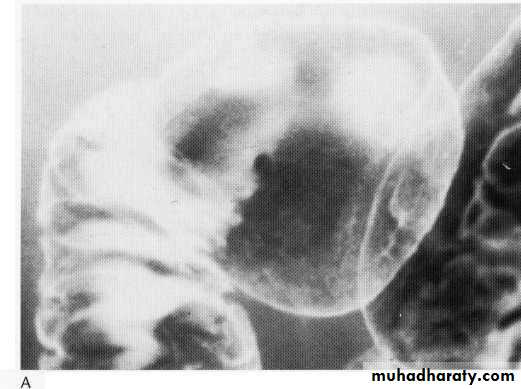

Benign du. Tumor arising from the medial wall